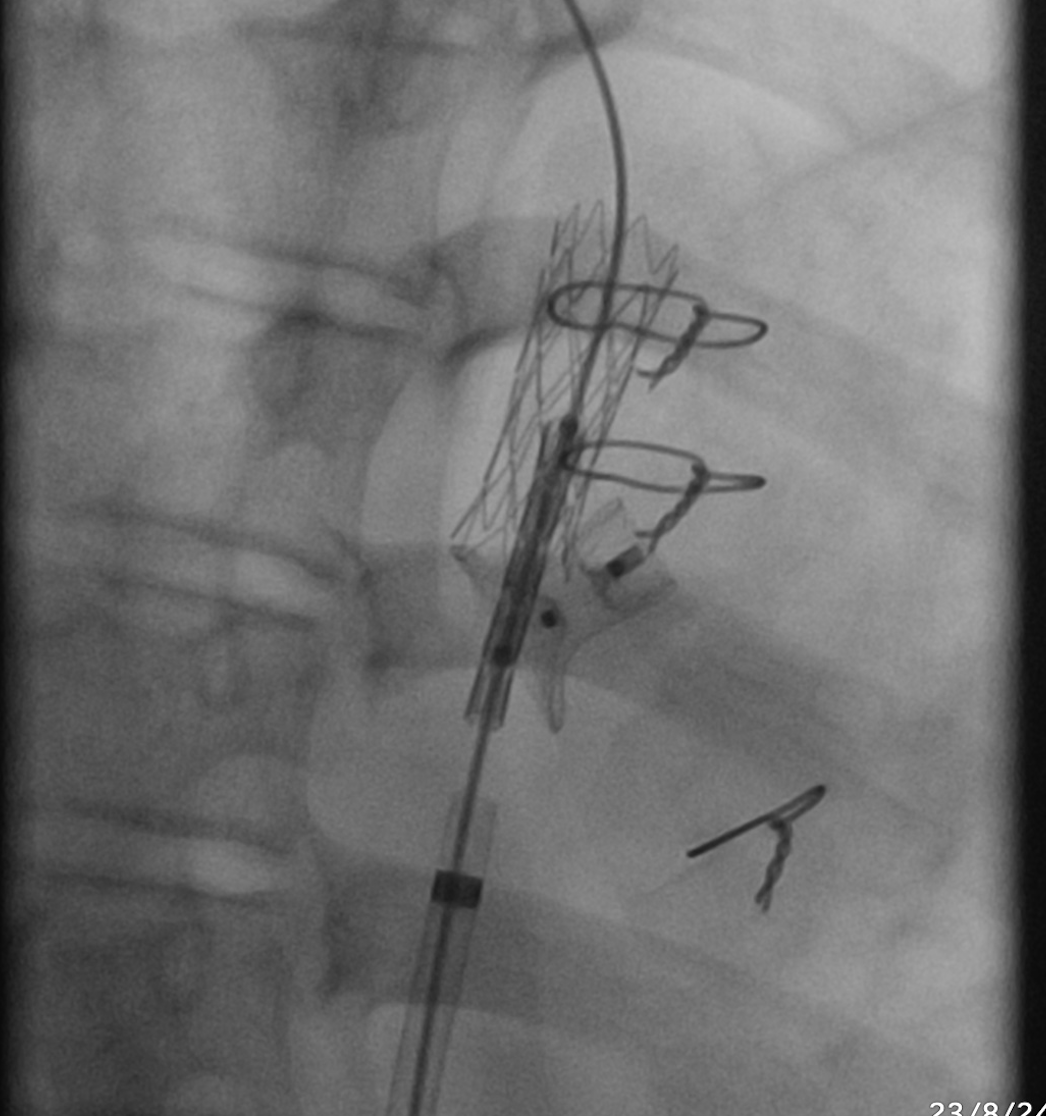

Firstly, an angiography was performed to confirm the positions of the CoA stent and PDA device. A 0.014” microwire (Transcend, Boston Scientific) was used to cross through the PDA device to reach the upper part of the aorta. A 5F guiding catheter was advanced toward the proximal stent but was unsuccessful. To assist with advancing the 5F guiding catheter, we used a 3.0 mm and 5.0mm balloon to dilate the opening beside the PDA device. An angiography was then conducted to assess the relative positions of the CoA stent and PDA device. We decided to deploy an additional stent to cover the distal part of the previous stent to direct the PDA device towards the pulmonary artery. A 7F delivery system was advanced to the optimal position, and a 21L AndraStent was successfully deployed. A 8.0mm high-pressure balloon (VACS III) was then used to further dilate the stent. The pressures in the ascending and descending aorta (below the stent) were recorded as 115mmHg and 90mmHg, respectively. Finally, an angiography confirmed the correct positioning of both the stent and the PDA device without complications.

Case Summary